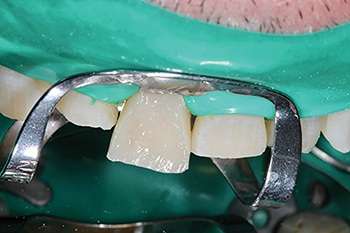

Shaw emphasized the importance of proper isolation for predictable bonding. Using a 90N clamp and rubber dam (Fig. 2), he sandblasted the tooth surfaces before etching to ensure bonding to a clean substrate. Much of the lower incisor work required bonding directly to dentin, making technique and moisture control essential to long-term success.

Fig. 2: Rubber dam isolation